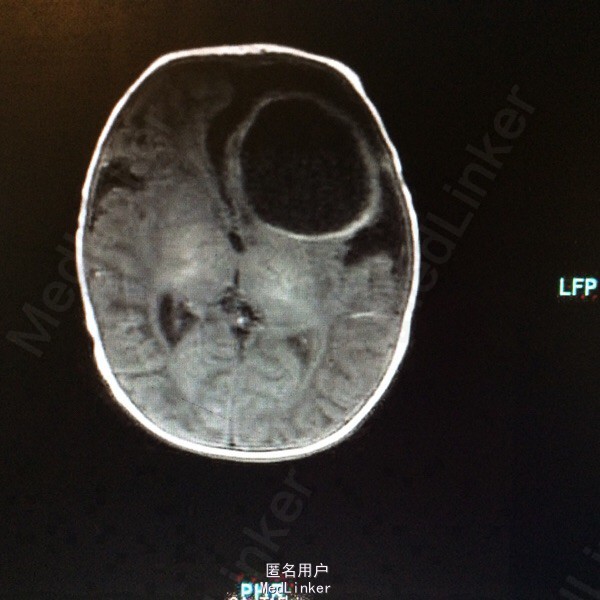

血常规:白细胞计数 WBC 18.61*10~9/L,中性粒细胞比例 Neu% 47.5%,淋巴细胞比例 Lym% 40.3%,血红蛋白 HGB 115g/L,血小板计数 PLT 433*10~9/L,CRP 79mg/L。大小便常规基本正常。肝肾功血糖心肌酶谱基本正常。降钙素原定量 PCT 1.80ng/ml。脑脊液生化 蛋白质 M-TP 528.1mg/灯笼,氯化物 CL 111.5mmol/L,葡萄糖 GLU 0.19mmol/L。 脑脊液常规检查(CSF) 细胞总数 110516.0×10~6/L,白细胞计数 108500.0×10~6/L,红细胞计数 2016×10~6/L,直接分类-单个核细胞比例 45%,直接分类-多核细胞比例 55%,颜色 黄色,透明度 浑浊,蛋白定性(Pandy's) 阳性(2+)。胸片:双肺改变考虑炎变,建议治疗后复查。颅内(彩超) :左侧脑实质囊性占位。磁共振增强扫描颅脑 :1、左侧额叶较大混杂信号囊状影,增强扫描壁明显强化,考虑脑脓肿;伴额、颞部蛛网膜下腔积液,请结合临床及其它检查。2、左侧侧脑室后角旁小结节影,增强扫描环形强化,考虑小脓肿可能。3、右侧侧脑室前角两处囊状影,未见强化,软化灶可能大,原因?PVL?